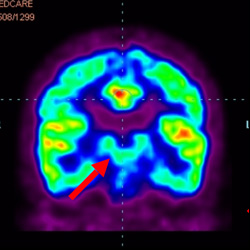

細胞治療前 PET CT 掃描顯示神經組織中的藍/黑色區域,表明腦癱引起的大腦損傷。

細胞治療后,藍色和黑色區域減少,并且看到更活躍的區域。這表明損傷減少并改善了大腦功能。

這證明細胞療法是治療腦癱兒童安全有效的方法。細胞療法可以更新大腦損傷的核心,并且可以通過 PET CT 掃描來監測大腦的改善情況。這些細胞療法與標準治療一起促進腦癱兒童的生長和改善。